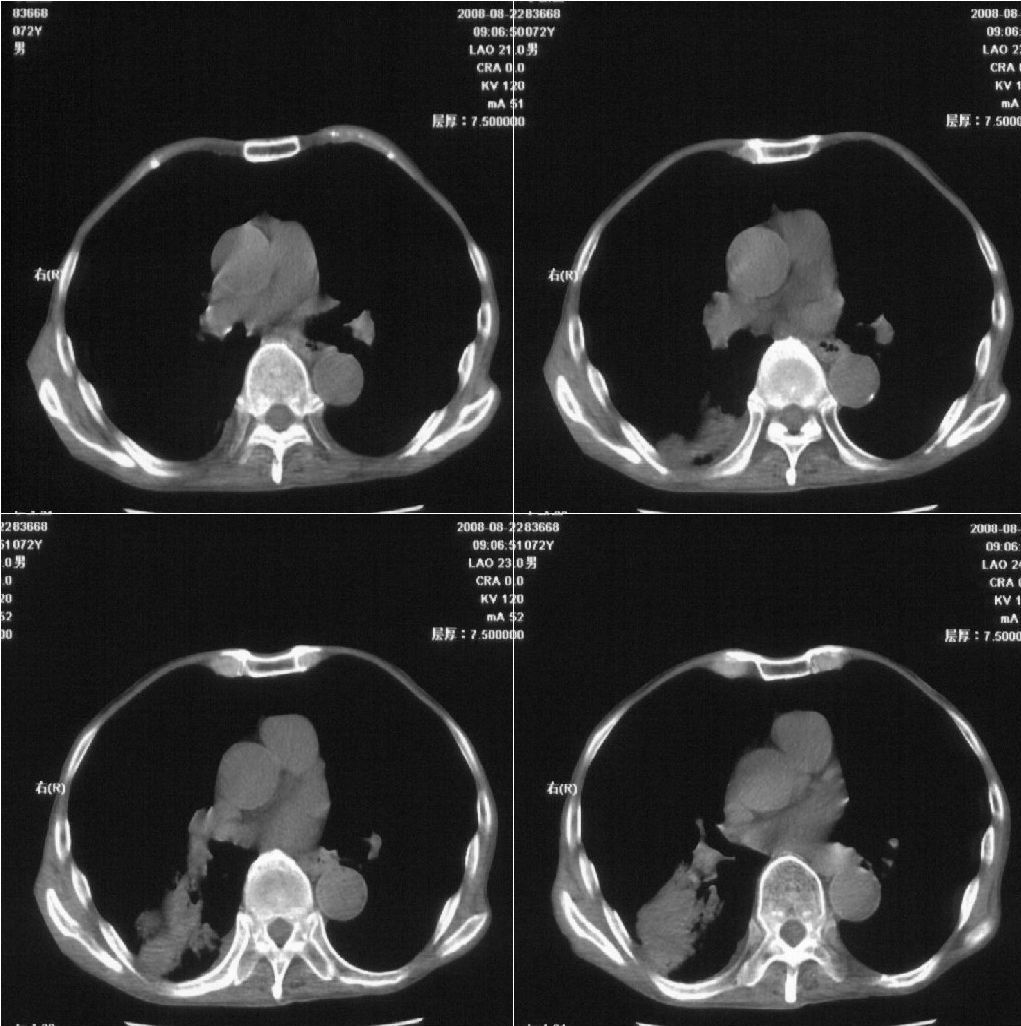

标题: CT15789:男性,72岁。食管癌术后14年。 [打印本页]

标题: CT15789:男性,72岁。食管癌术后14年。

痰培养:见葡萄球菌,霉菌少量生长。(此片系外院所作,仅提供了增强后的ct值为100hu,中心的坏死部分无强化,患者现在身体状况欠佳,为恶液质状态)

考虑肺癌可能性大伴阻塞性炎症

周围型肺癌可能性大.

考虑右肺下叶感染性病变(肺脓肿?);建议抗炎治疗后复查。

病人无发热,消瘦,考虑ca